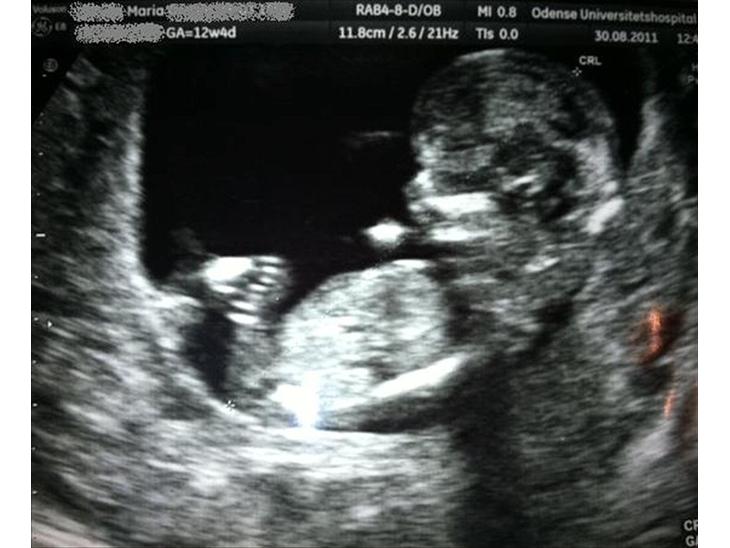

her vil der løbende komme billeder af vores lille baby og billeder udefra maven når vi når hen så vi kan se noget :)